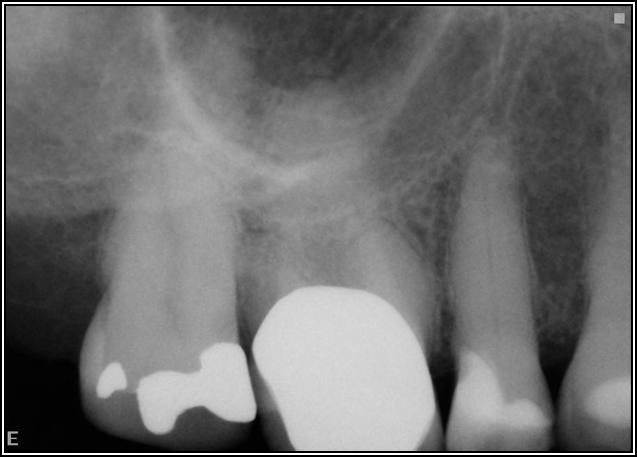

Fig 8. Bitewing revealed decay and other problems.

Figure 8

With the bitewing shown in Figure 8, it became clear there was gross decay in tooth No. 3 that could not be seen on the PA, and there was a periodontal defect, a pulp stone, in No. 2. There was also a class V lesion revealing the bruxism, flat occlusion, multiple restorations in No. 30, a post in No. 31, and decay on No. 2 as well. The post in No. 31 was useless because when a post is placed, it must be the right length, width, and size. If the post is too short, there will be a greater fulcrum and the tooth will break. If it is too long, the clinician can break it by wedging it. If it is too short, it will not hurt the tooth, but it will not provide any valuable function. It is overall preferable to do posts in teeth having just single restorations rather than abutments for bridges because those teeth are already under greater force. If the technique is not performed correctly, iatrogenic issues may result.